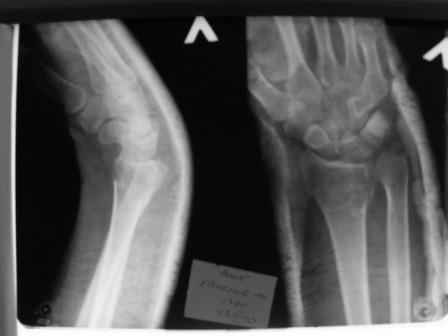

Уважаемые коллеги.Прошу обсудить случай лечения перелома дистального метаэпифиза лучевой кости. Ситуация скандальная и крайне неблагоприятная. Больная с патологической обстоятельностью мышления, склонностью к сутяжничеству, патологическими умозаключениями, не поддающимися коррекции (см. психиатрию, правда офиц. диагноза нет). В данном случае есть ряд ошибок с нашей стороны, прежде всего в отношении качества ведения документации (за что получил административное взыскание, по делом мне дураку). В остальном- придерживались в лечении подхода классический советской школы. Так как умную операцию…… сами знаете… 15.12- перелом луча в Москве. Там же репозиция, гипс. Дальнейшее лечение у нас в ЦРБ. 20.12.- вторичное смещение в гипсе21.12- под внутривенным наркозом- репозиция, гипсовая лонгета. Дальше начинается самое интересное. После репозиции больная заявила, что я (репозицию делал я) порвал ей все связки в суставе, посинел у нее 5 палец, якобы я за него тянул и т. д. На самом деле на 2 сутки после репозиции рука немного отекла и было незначительное сдавление гипсом, который был ослаблен. Дальнейшее лечение консервативное. Через 6 недель- гипс снят, назначено ЛФК. Пациентка крайне недовольна. Говорит, что на снимке у нее выступает кость, я ей сломал руку и.т.д. В общем началось. Пациентка прочитала в интернете наверное все, что есть по данной травме.По заключениями рентгенологов и консультанта из КДЦ областной больницы - стояние отломков допустимое. Объективно говоря- снижена высота лучевой кости, диастаз лучелоктевого сочленения, и не сросся шиловидный отросток. однако на РКТ при сравнении с другой стороной- разница незначительная. Дальше в одной из больниц нашей области и одной из больниц Москвы (вроде бы КГБ 53) врачи сказали, что репозиция сделана плохо. Нужна операция (восстановить длину лучевой кости), даже один из них предложил РЕДРЕССАЦИЮ (хи-хи) с наложением аппарата Илизарова. Что это для данной больной- радость неописанная. (см. описание психического статуса). Ничем другим, кроме зарабатывания дешевого авторитета объяснить данный факт не могу.Кстати, у больной еще нейропатия локтевого нерва.Для разрешения конфликта больная направлена на консультацию в ЦИТО на 03.03.11.

Теперь вопросы: 1.Прошу объективно оценить качество нашей репозиции на момент 21.12. (неужели так плохо?). Что на снимках при снятии гипса- сам вижу. 2. сравнить снимки РКТ (с двух сторон)- так ли велико укорочение лучевой кости и лучелоктевой диастаз. 3. Ваши мнения, в отношении целесообразности оперативного лечения учитывая ВСЕ вышеизложенное. 4. На всякий случай для суда- мог ли я тракцией в 2- 3 кг за 1 и 2 пальцы под внутривенным наркозом неправильно вколотить отломки и травмировать локтевой нерв. Кстати, в США если врач пациенту говорит, что его плохо лечили- то этого врача лишают лицензии. У нас наооборот- обгадить другого милое дело. И это процветает. От себя же могу сказать, что никто в нашем отделении так не поступает. Коллеги, будьте осторожны в своих высказываниях. От осложнений и ошибок никто не застрахован. А в данном случае многое будет зависеть от заключения консультантов поликлиники ЦИТО, куда больная направлена областным травматологом на 03.03 для решения вопроса о дальнейшей тактики лечения. С уважением ко всему травматологическому сообществу Дедок Михаил.

1. РЕПОЗИЦИЯ сделана качественно(ОСНОВНЫЕ 2 УГЛА ВЫСТАВЛЕНЫ ПРАВИЛЬНО ) , но перелом нестабильный и склонен к втор смещению . Поэтому мы стараемся все переломы со смещением фиксировать 3-МЯ спицами по GRIN методике .

1. Репозиция от 21.12.10 была выполнена лучше, чем первичная.